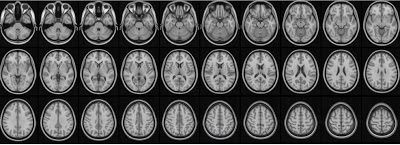

حالة وعينا تتغير بشكل ملحوظ أثناء مراحل نومنا العميق، تمامًا كما يحدث في حالة الغيبوبة أو تحت التخدير العام. لطالما اعتقد الباحثون - ولكن لم يكونوا متأكدين - أن نشاط الدماغ ينخفض عندما ننام. تُجرى معظم الأبحاث على النوم باستخدام تخطيط كهربية الدماغ «EEG»، وهي طريقة تنطوي على قياس نشاط الدماغ بواسطة أقطاب كهربائية موضوعة على طول فروة رأس الشخص. ولكن، أنجالي تارون Anjali Tarun، طالبة دكتوراه في مختبر معالجة الصور الطبية التابع لكلية الهندسة في جامعة البولتيكنيك الفدرالية في لوزان EPFL، قررت دراسة نشاط الدماغ أثناء النوم باستخدام التصوير بالرنين المغناطيسي MRI.

وفقًا لديميتري ڤان دي ڤيل Dimitri Van De Ville، الذي يرأس المختبر، ”مسوحات التصوير بالرنين المغناطيسي تقيس النشاط العصبي بجس استجابة ديناميكا الدم «1» لبنويات في كل الدماغ، وبالتالي تزودنا بمعلومات مهمة بالإضافة إلى المعلومات التي يوفرها تخطيط كهربية الدماغ“. خلال هذه التجارب، اعتمدت تارون على تخطيط كهربية الدماغ لتحديد متى يغلب النعاس على المشاركين في الدراسة وينامون، وتحديد مراحل النوم المختلفة. ثم قامت بفحص صور التصوير بالرنين المغناطيسي لوضع خرائط مكانية للنشاط العصبي وتحديد حالات الدماغ المختلفة.